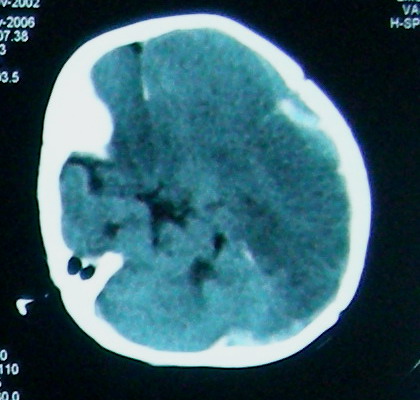

左侧大脑半球和右侧额叶大片低密度影,脑沟及外侧裂池消失,左侧脑室闭合,考虑脑梗塞伴有水肿。

考虑:1、左额颞顶慢性硬膜下血肿(可能为产伤所致);

2、蛛网膜下腔出血;

3、左侧大脑半球及右额叶脑肿胀、梗塞(缺血性脑梗塞为脑疝所致)。

结合临床考虑1、脓毒栓子致左侧大脑半球及右侧额叶梗塞。2、左侧额颞顶部硬膜下血肿形成.3、镰下疝形成。

左额颞顶慢性硬膜下血肿(可能为产伤所致);蛛网膜下腔出血,已明确,至于左侧大脑半球大片低密度影并脑组织肿胀,考虑:梗塞导致缺血缺氧性改变.至于梗塞原因随诊观察吧!

左侧大脑半球和右侧额叶大片低密度影,脑沟及外侧裂池消失,左侧脑室闭塞,左侧蛛网膜下腔片絮状高密度影,结合病儿高热、脑膜刺激征(+),考虑:炎脑,脑水肿,左侧蛛网膜下腔出血。至于出血原因,应该为高热所致维生素c需要量增加,而补给不足所致维生素c缺乏,抑或是使用抗惊厥药影响维生素k代谢,使凝血发生障碍而出血。当然,一切都是猜测,需要临床进一步检查验证。